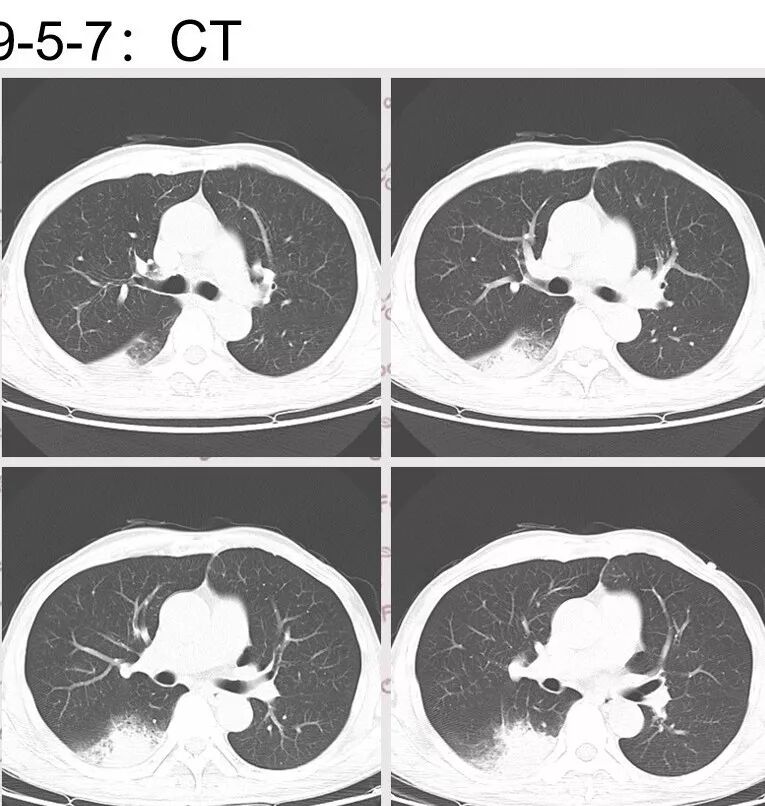

胸部CT:右肺下叶背段实变,广基底,糊墙,长轴与胸膜平行,周围晕,支气管进入堵塞,纵隔窗可见低密度坏死,实变内小空洞?脑部不会看。

胸CT:右肺下叶背段实变影,内可见小空泡,病灶与胸膜呈宽基底,实变病灶周围存在毛玻璃影,纵隔窗可见病灶内存在低密度,增强可见病灶强化,并见病灶内低密度区。头MRI不会看。

右肺下叶背段实变,广基底,糊墙,长轴与平行胸膜,周围有晕,支气管进入堵塞,可见低密度坏死及小空泡。颅内多发环形强化灶,符合脑脓肿三层结构,结合临床,考虑:感染性病变,隐球菌?鉴别肺克。

右肺下叶大片实变

我们回头看肺内的,病灶位于下叶背段,可惜没重建

近肺门区见一坏死腔,内壁较清楚,空泡在周围

2.影像右肺下叶大片高密度影,整体边界模糊柔和,中央见圆形液化区及微小气泡影,内壁相当光整,环形强化,未见明确壁结节。双肺门及纵隔未见增大淋巴结。这样的病灶更符合细菌性肺脓肿,以肺炎克雷伯杆菌感染最为常见。